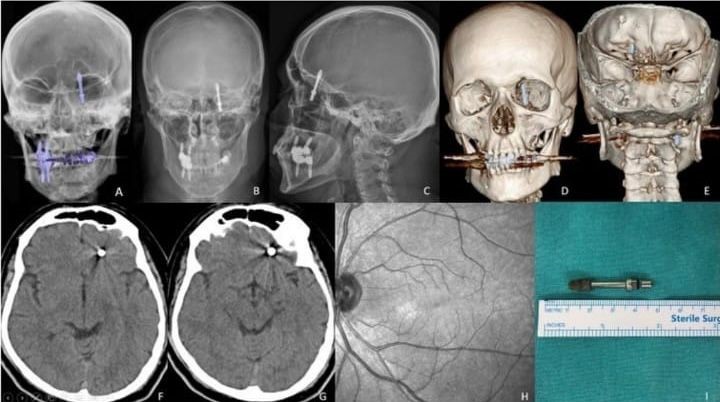

İddiaya göre, implantı çeneye yerleştirmek isteyen doktorun yanlış müdahalesi sonrası vida, Yılmaz’ın çene kemiğini delip kafatasına saplandı. Acı içinde kalan Yılmaz’ın yaşadığı baygınlık sonrası film çeken Doktor A.D., vidanın kafatasında olduğunu görünce hemen kendi aracıyla Yılmaz’ı bir hastaneye bıraktı. Hastanede çekilen tomografi sonrası gözlerine inanamayan doktorlar, 2 çocuk babası adamı hemen ameliyata aldılar. Saatlerce süren operasyon sonrası hayata tekrar dönen Yılmaz, günlerce taburcu olmayı bekledi. Sağlığına dönen Yılmaz, kendisine yanlış müdahale yapan diş hekimini aradığında ise ikinci bir şoku yaşadı. Yaptığı ödemenin iadesini isteyen Yılmaz’a doktor tarafından ret cevabı gelince Yılmaz, yargının yolunu tuttu.

Kendisini uyarmasına rağmen dinlemediğini ifade eden Yılmaz, “Daha sonra dişlerimi çekip, aynı gün implant uygulaması yaparken, işlemde kullandığı cihazın bozuk olduğunu sekreterine söyledi. Bu kez de işlemi eliyle yapmaya başladı. Vidayı yerleştirmeye çalışırken, aşırı yüklendiğini fark ettim. Bunu kendisine söyledim, kemik sesi geldiğini ifade ettim. Fakat bu kez de bana bunun normal olduğunu söyledi. Ama vidayı zorlarken, vida çene kemiğimi delip göz duvarının arkasından beyin omurilik sıvısının olduğu bölgeye saplandı. Ben acıdan dolayı bağırınca röntgen çektirdi” dedi.

Doktorun kendisini hastaneye bırakıp kaçtığını iddia eden Yılmaz, “Durumun ciddiyetini anlayınca beni Uludağ Üniversitesi Hastanesinin Acil bölümüne getirip gitti. Burada yapılan inceleme sonrası vidanın beyin omurilik sıvısının olduğu yere saplandığı görüldü. Daha sonra uzman hekimler bir araya gelip, ameliyat için karar aldılar. Ameliyat öncesi bana hayatımı kaybedebileceğimi söylediler. Ben artık çocuklarımla helalleşip vedalaştım. Çok şükür ameliyattan sağ salim çıktım. Bu süreçlerde diş hekimi hiç bir zaman yanımda olup mağduriyetimi gidermedi, hatta ödediğim ücreti dahi geri iade etmedi. Üstüne üstelik benimle dalga geçer gibi konuştu. Bunların hepsi belgeli. Ben yetkililerden devlet büyüklerimizden bu konuyla ilgilenilmesini istiyorum. Benim iki çocuğum var. Bana bir şey olsaydı bunların hesabını kim verecekti ? Şimdi dava sürecine girdik. Kendisinden şikayetçi oldum” diye konuştu.

Öte yandan Yılmaz’ı sağlığına kavuşturan doktorların başarılı ameliyatı, Amerika’da literatüre girip dergilere konu oldu.